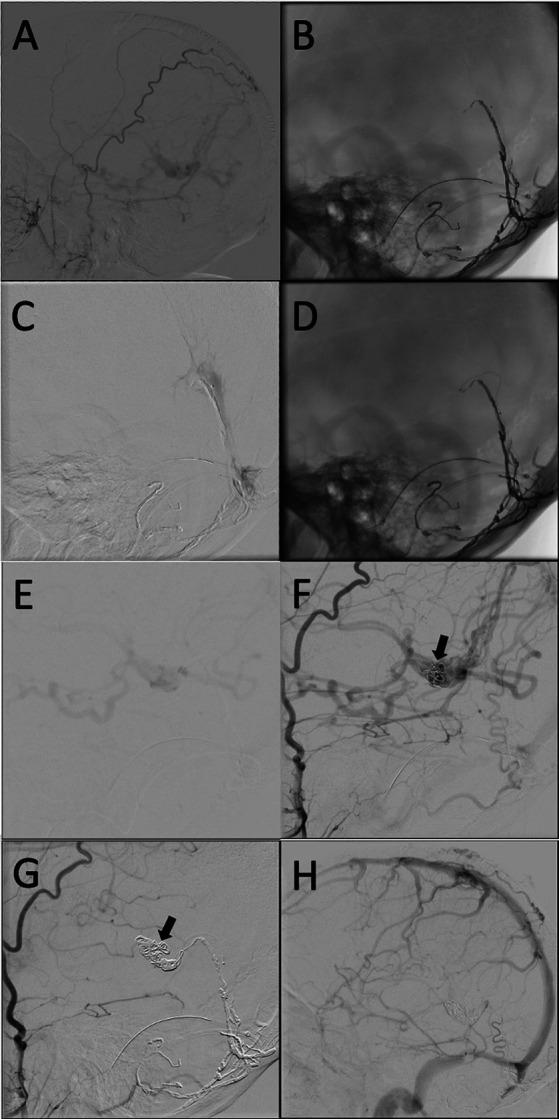

Case report: Transvenous coil embolization of a high-grade Galenic dural arteriovenous fistula.

The patient is a 54-year-old female who presented with a 2-year history of progressive headaches, cognitive decline, and papilledema. A cerebral angiogram demonstrated a complex dAVF to the vein of Galen (VoG). She underwent transarterial embolization with Onyx-18 which resulted in minimal reduction in arterial venous shunting. She subsequently underwent a successful transvenous coil embolization resulting in complete occlusion of dAVF. The patient's postoperative course was complicated by interventricular hemorrhage; however, she had a remarkable clinical recovery with resolution of headaches and improvement in cognitive function. A follow-up angiogram completed 6  months post-embolization demonstrated very mild residual shunting.